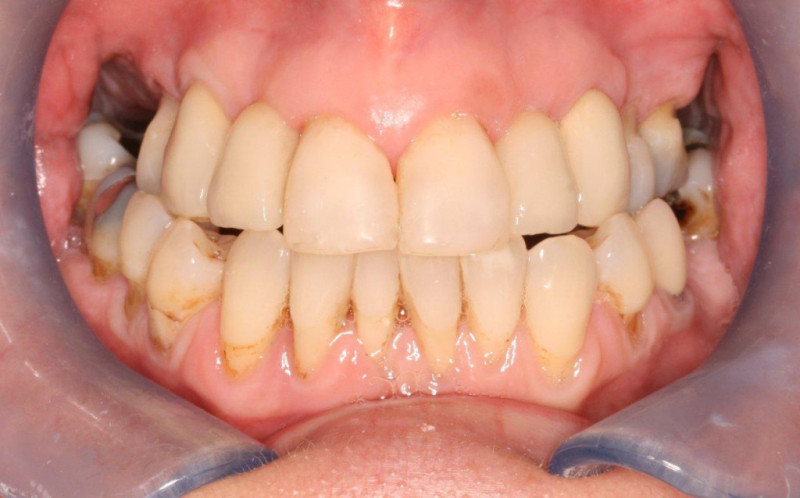

Inflammation of the gums is initially called gingivitis. People who are susceptible to gum disease may progress to get periodontal disease.

Over time, Periodontal disease can damage your ability to bite and lead to tooth loss.

To make sure this doesn't happen, we start treatment promptly to stop the process and maintain your long-term dental health.

Our Periodontal treatment is carried out by either Robert Eades's or Kelly Tachell our Hygienist and Therapist, this is to ensure that the foundations are maintained fully.

A six sextant gum health score will be accessed and recorded at all  examination appointments.